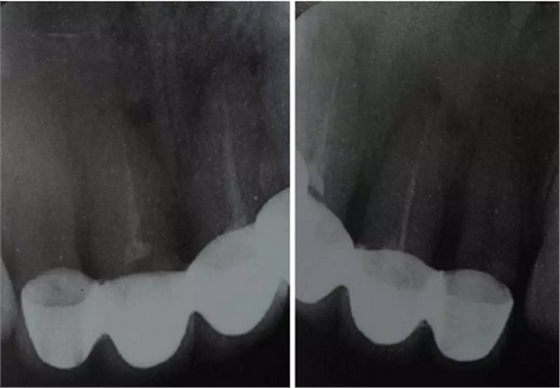

臨床檢查可見12~22烤瓷聯(lián)冠修復(fù),冠邊緣不密合,齦緣外形不協(xié)調(diào),牙齦紅腫,22烤瓷冠崩瓷。根管治療不完善,牙齦根尖部位有瘺管,X線影像顯示11、21根尖有陰影。上頜前突,上前牙修復(fù)體舌傾。 患者治療前口內(nèi)像 側(cè)位像 治療前曲面體層片 治療前前牙區(qū)X線片

董艷梅教授:修復(fù)前如有以下情況,應(yīng)考慮進(jìn)行根管再治療:① X線片顯示前次根管治療不完善;② X線片顯示患牙根尖周新增病變或根尖周病變范圍擴(kuò)大或未見縮小;③ 患牙在前次根管治療后長期有癥狀或臨床體征。要明確的是,首次根管治療失敗后原則上應(yīng)首選非手術(shù)根管再治療。根尖手術(shù)原則上應(yīng)該在完成完善的根管治療后進(jìn)行。